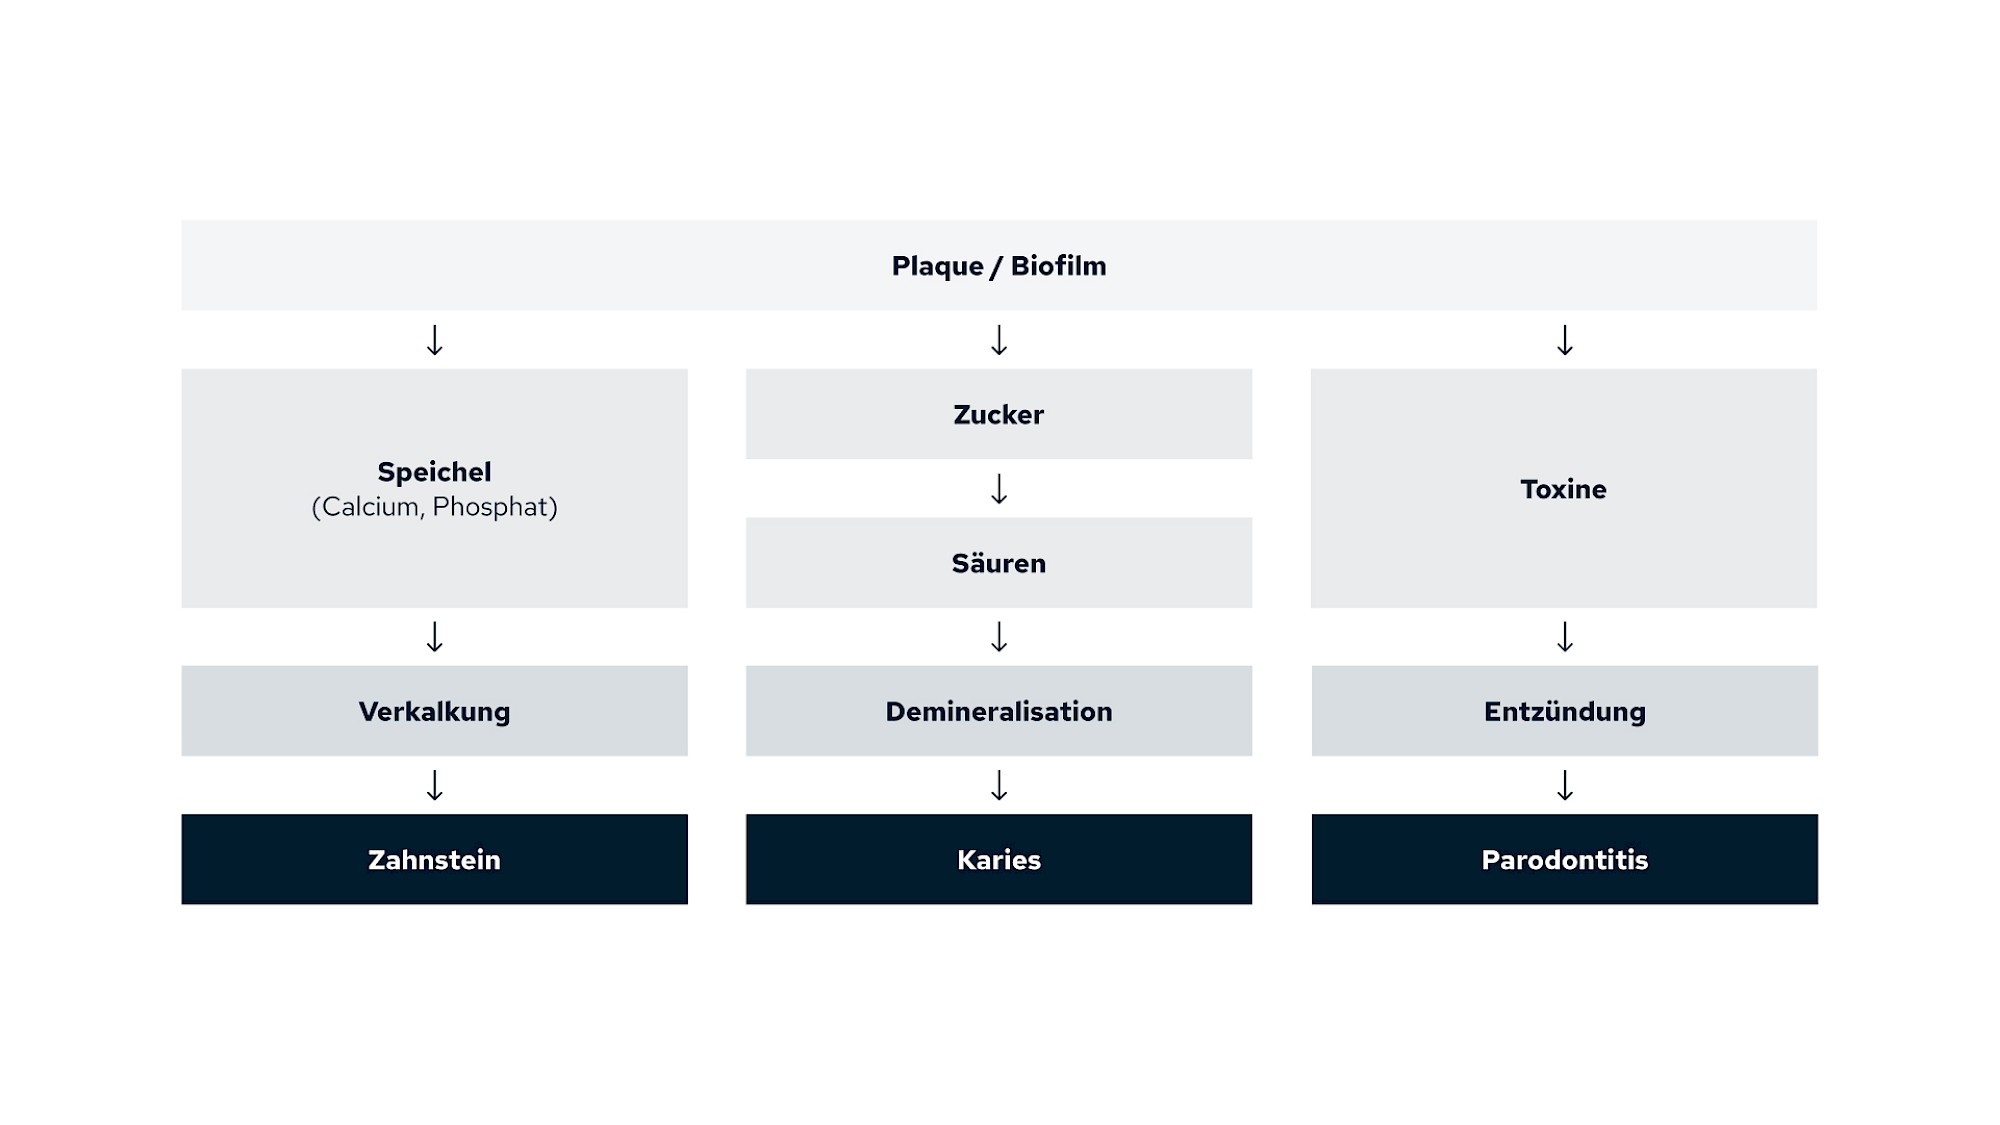

Plaque (Biofilm): Was kann sich daraus entwickeln?

Aus Plaque können sich verschiedene krankhafte Prozesse entwickeln:

- Mineralien aus dem Speichel lagern sich in die Plaque ein: Zahnstein & Konkrement

- Bakterien in der Plaque lösen durch Stoffwechselprodukte die Zahnoberflächen an bzw. auf: Karies

- Bakterien in der Plaque lösen Abwehrreaktionen des Körpers aus: Zahnfleischbluten